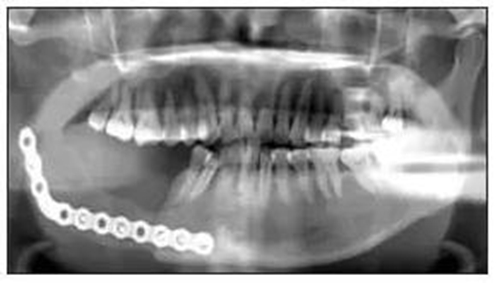

免疫組織化學(xué)結(jié)果:S100彌漫陽性、CD21陰性、CD57陰性、CR陽性、結(jié)蛋白陰性、鈣調(diào)結(jié)蛋白陰性、ALK陰性、PCK陰性、Ki-67表達2%~5%陽性(圖2)。1.5 隨訪患者術(shù)后切口愈合良好,牙無松動,咬合關(guān)系良好。術(shù)后復(fù)查顯示傷口愈合良好,骨斷端生長良好(圖3)。

圖3 術(shù)后全景片